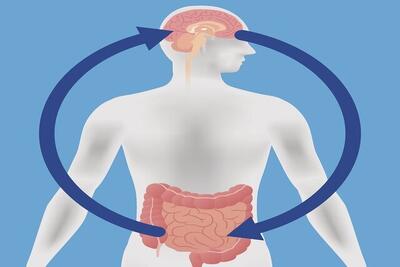

عادت فروکردن انگشت در بینی (رینوتیلکسومانیا) میتواند میکروبهایی وارد حفره بینی کرده و باعث التهاب مغز شود، که با شروع بیماری آلزایمر مرتبط است.